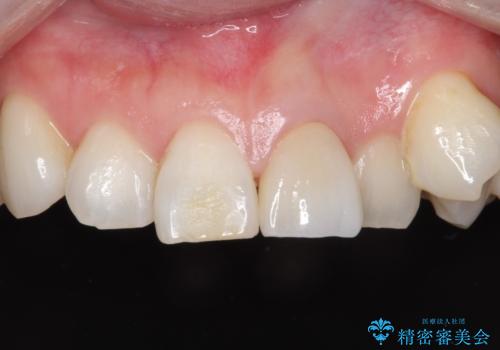

前歯を綺麗にしたい オールセラミッククラウン

- 他院で前歯の変色をダイレクトボンディングにて修復治療しておりましたが、審美障害を主訴に来院されました。

根管治療後、オールセラミックにて治療を行っております。

ダイレクトボンディングはセラミックに比べ経年劣化しやすい材料です。

今回はオールセラミッククラウンによる治療を行いより審美的な修復ができました。